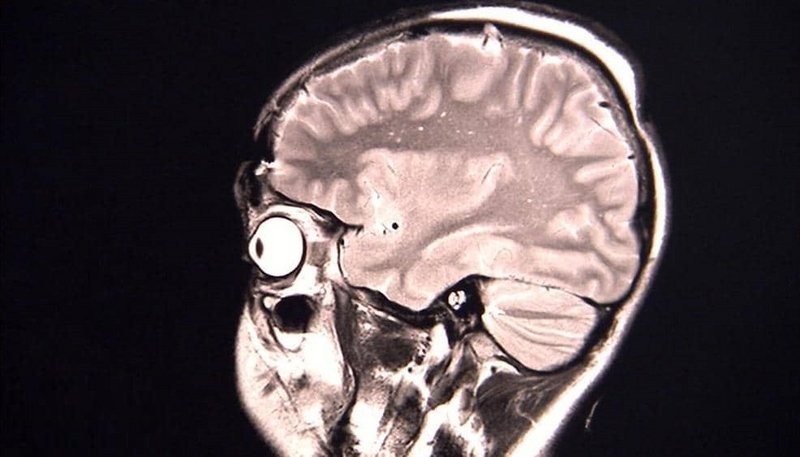

ورغم أن ثلاث حالات ليست كافية للوصول إلى استنتاجات على نطاق واسع بشأن الوباء، إلا أن العلماء يعتقدون أن الأعراض ربما تكون نتيجة للاستجابة المناعية التي تسبب التهاباً في أجزاءٍ معينة في الدماغ.

وحسب "سكاي نيوز عربية"، نشر الباحثون نتائج الدراسة في دورية "غاما" العلمية، واعتمدت الدراسة على نتائج الفحص الطبي للمرضى الثلاثة أثناء علاجهم في المستشفيات إثر مشكلات نفسية عانوها.